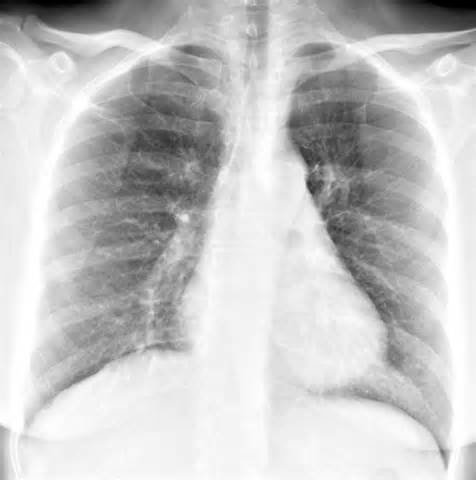

- Рентгенография органов грудной клетки проводится только при подозрении на пневмонию или аспирацию (проникновение в дыхательные пути инородного тела). А также при наличии длительного кашля (более 2 недель) или односторонних хрипов.

На рентгенограмме будут признаки бронхита (усиление легочного рисунка)